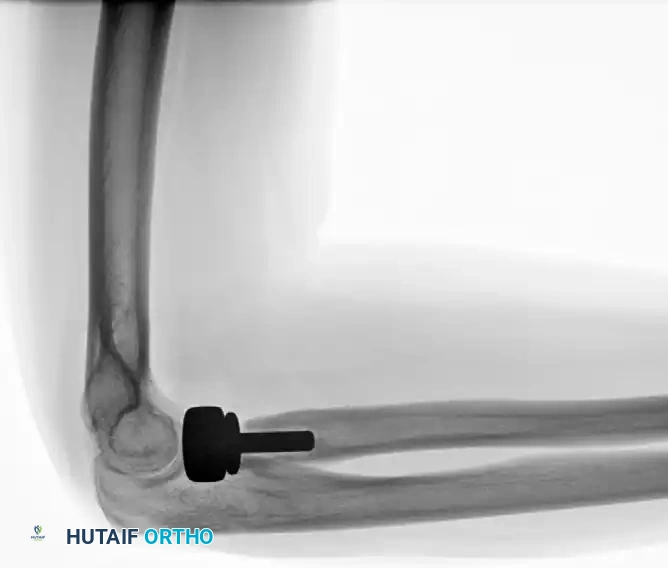

If concentric stability cannot be achieved despite adequate bony and ligamentous reconstruction, a hinged dynamic external fixator must be applied. The external fixator maintains joint congruity while allowing the early active motion necessary for cartilage nutrition and prevention of capsular contracture.